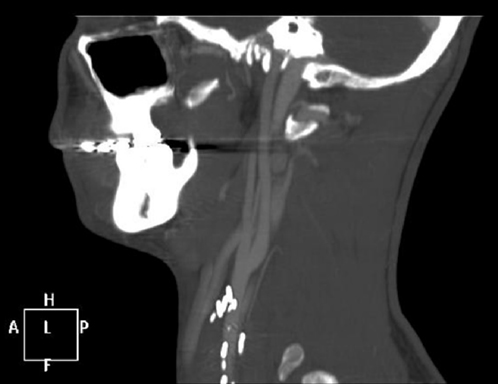

Figure 3 Sagittal reconstructed Computer Tomography carotid angiogram demonstrates an oval shaped homogenously enhancing mass posterior to the left internal carotid artery.